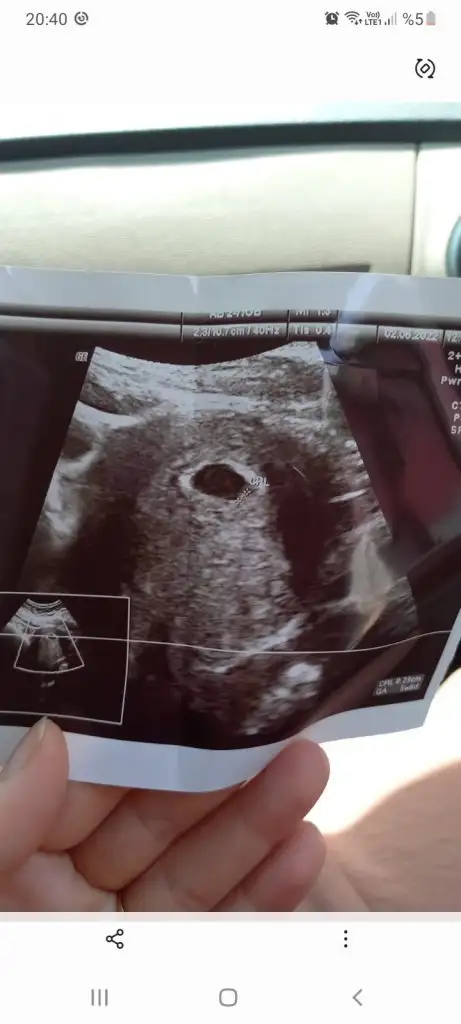

prenses gibi12+5 günlük karından çekildi yorum yapabilirmisiinPasha22

bu paşa canım maşallahMerhaba nursu 11 haftalik atmistim prenses gibi demistin bugün 13 +2 hafta olduk özel hastanede doktor %90 erkek dedi son foto attım yeniden baksana

doktor öyle dediyse bize söz düşmezYüzde 80 erkek dediler doğru mu sizce